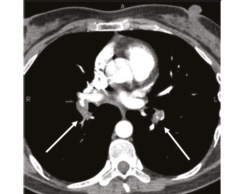

В 1993 г. на основании характерных признаков электрокардиограммы (ЭКГ) при профилактическом обследовании диагностирован феномен Вольфа–Паркинсона–Уайта. Клинических проявлений, снижающих качество жизни, пациентка не отмечала. К врачам далее не обращалась. В связи с появлением в 2015 г. одышки, перебоев в работе сердца, сердцебиения наблюдалась у участкового терапевта с диагнозом: ишемическая болезнь сердца, гипертоническая болезнь. Эхокардиография (ЭхоКГ), нагрузочные тесты не проводились. На фоне приема лозартана 25 мг/сут достигнуты целевые значения АД. В январе 2017 г. в связи с зарегистрированным на ЭКГ пароксизмом тахикардии с узкими комплексами QRS пациентка в порядке скорой помощи поступила с диагнозом «пароксизмальная суправентрикулярная тахикардия» в ЦРБ, где ритм был медикаментозно восстановлен. Далее в краевой больнице проведено внутрисердечное электрофизиологическое исследование и по его результатам – радиочастотная аблация дополнительных проводящих путей. Послеоперационный период протекал без осложнений. Однако в июне 2017 г. вновь появилась одышка при выполнении привычного объема физической нагрузки. По данным ЭКГ и рентгенограммы органов грудной клетки патологии не выявлено. Вскоре появилось кровохарканье (в течение 3 дней), и пациентка была направлена к фтизиатру, которым исключен туберкулез легких. 27.07.2017 на фоне значительного усиления одышки, выраженной тахикардии она потеряла сознание и в порядке скорой помощи доставлена в дежурный стационар, где травматологом и неврологом исключены сотрясение головного мозга и закрытая черепно-мозговая травма. Пациентка отпущена домой. В связи с сохраняющейся одышкой при подъеме на один лестничный пролет в августе 2017 г. по собственной инициативе она обратилась к кардиологу. При проведении ЭхоКГ выявлены увеличение правых камер сердца и признаки их объемной перегрузки. С предварительным диагнозом ТЭЛА пациентка направлена в дежурный стационар, где в экстренном порядке проведена спиральная компьютерная томография (СКТ) с контрастированием легочной артерии. Выявлены признаки легочной тромбоэмболии крупных и средних ветвей легочной артерии (ЛА) с обеих сторон (рис. 1–4). При целенаправленном сборе анамнеза выяснилось, что в течение 3 лет (с 2014 г.) пациентка принимает Линдинет 20 мг – монофазный пероральный контрацептив (этинилэстрадиол + гестоден), назначенный гинекологом с целью контрацепции. По данным ультразвукового исследования вен нижних конечностей выявлен тромбоз суральных вен справа. Линдинет отменен. На фоне лечения антикоагулянтами (гепарин, эноксапарин) состояние женщины несколько улучшилось. Она переведена на варфарин, который далее заменен на апиксабан в дозе 10 мг 2 раза в день.

Рис. 1: а – тромбы в верхнедолевой ветви левой ЛА; б – верхнедолевая ветвь левой ЛА проходима. | |

Рис. 2: а – тромбы в правой ЛА и нижнедолевой ветви левой ЛА; б – правая ЛА и нижнедолевая ветвь левой ЛА проходимы. | |

Рис. 3: а – тромбы в нижнедолевой ветви левой ЛА и нижнедолевой ветви правой ЛА; б – сохраняется тромбоз нижнедолевой ветви правой ЛА. | |

Рис. 4: а – тромбы в левой ЛА и ее ветвях; б – тромбоза левой ЛА (нисходящей ветви) не выявлено, сохраняется тромбоз нижнедолевой ветви левой ЛА. | |

По данным чресприщеводной ЭхоКГ тромбоза камер сердца не обнаружено, однако уровень D-димера – более 250 мкг/л. Исследования в отношении патологии гемостаза выявили значительный дефицит протеинов С и S. Проведена замена апиксабана на ривароксабан 15 мг 2 раза в сутки с последующим переводом на прием ривароксабана 20 мг 1 раз в сутки в связи с большей биодоступностью последнего. Также с целью усиления антитромботического эффекта к терапии добавлен клопидогрел в дозе 75 мг в сутки. При проведении СКТ органов грудной клетки с контрастированием легочной артерии 26.09.2018 выявлена положительная динамика (см. рис. 1, б, рис. 4). Состояние стабилизировалось, рецидивы одышки прекратились. От имплантации кава-фильтра пациентка отказалась.